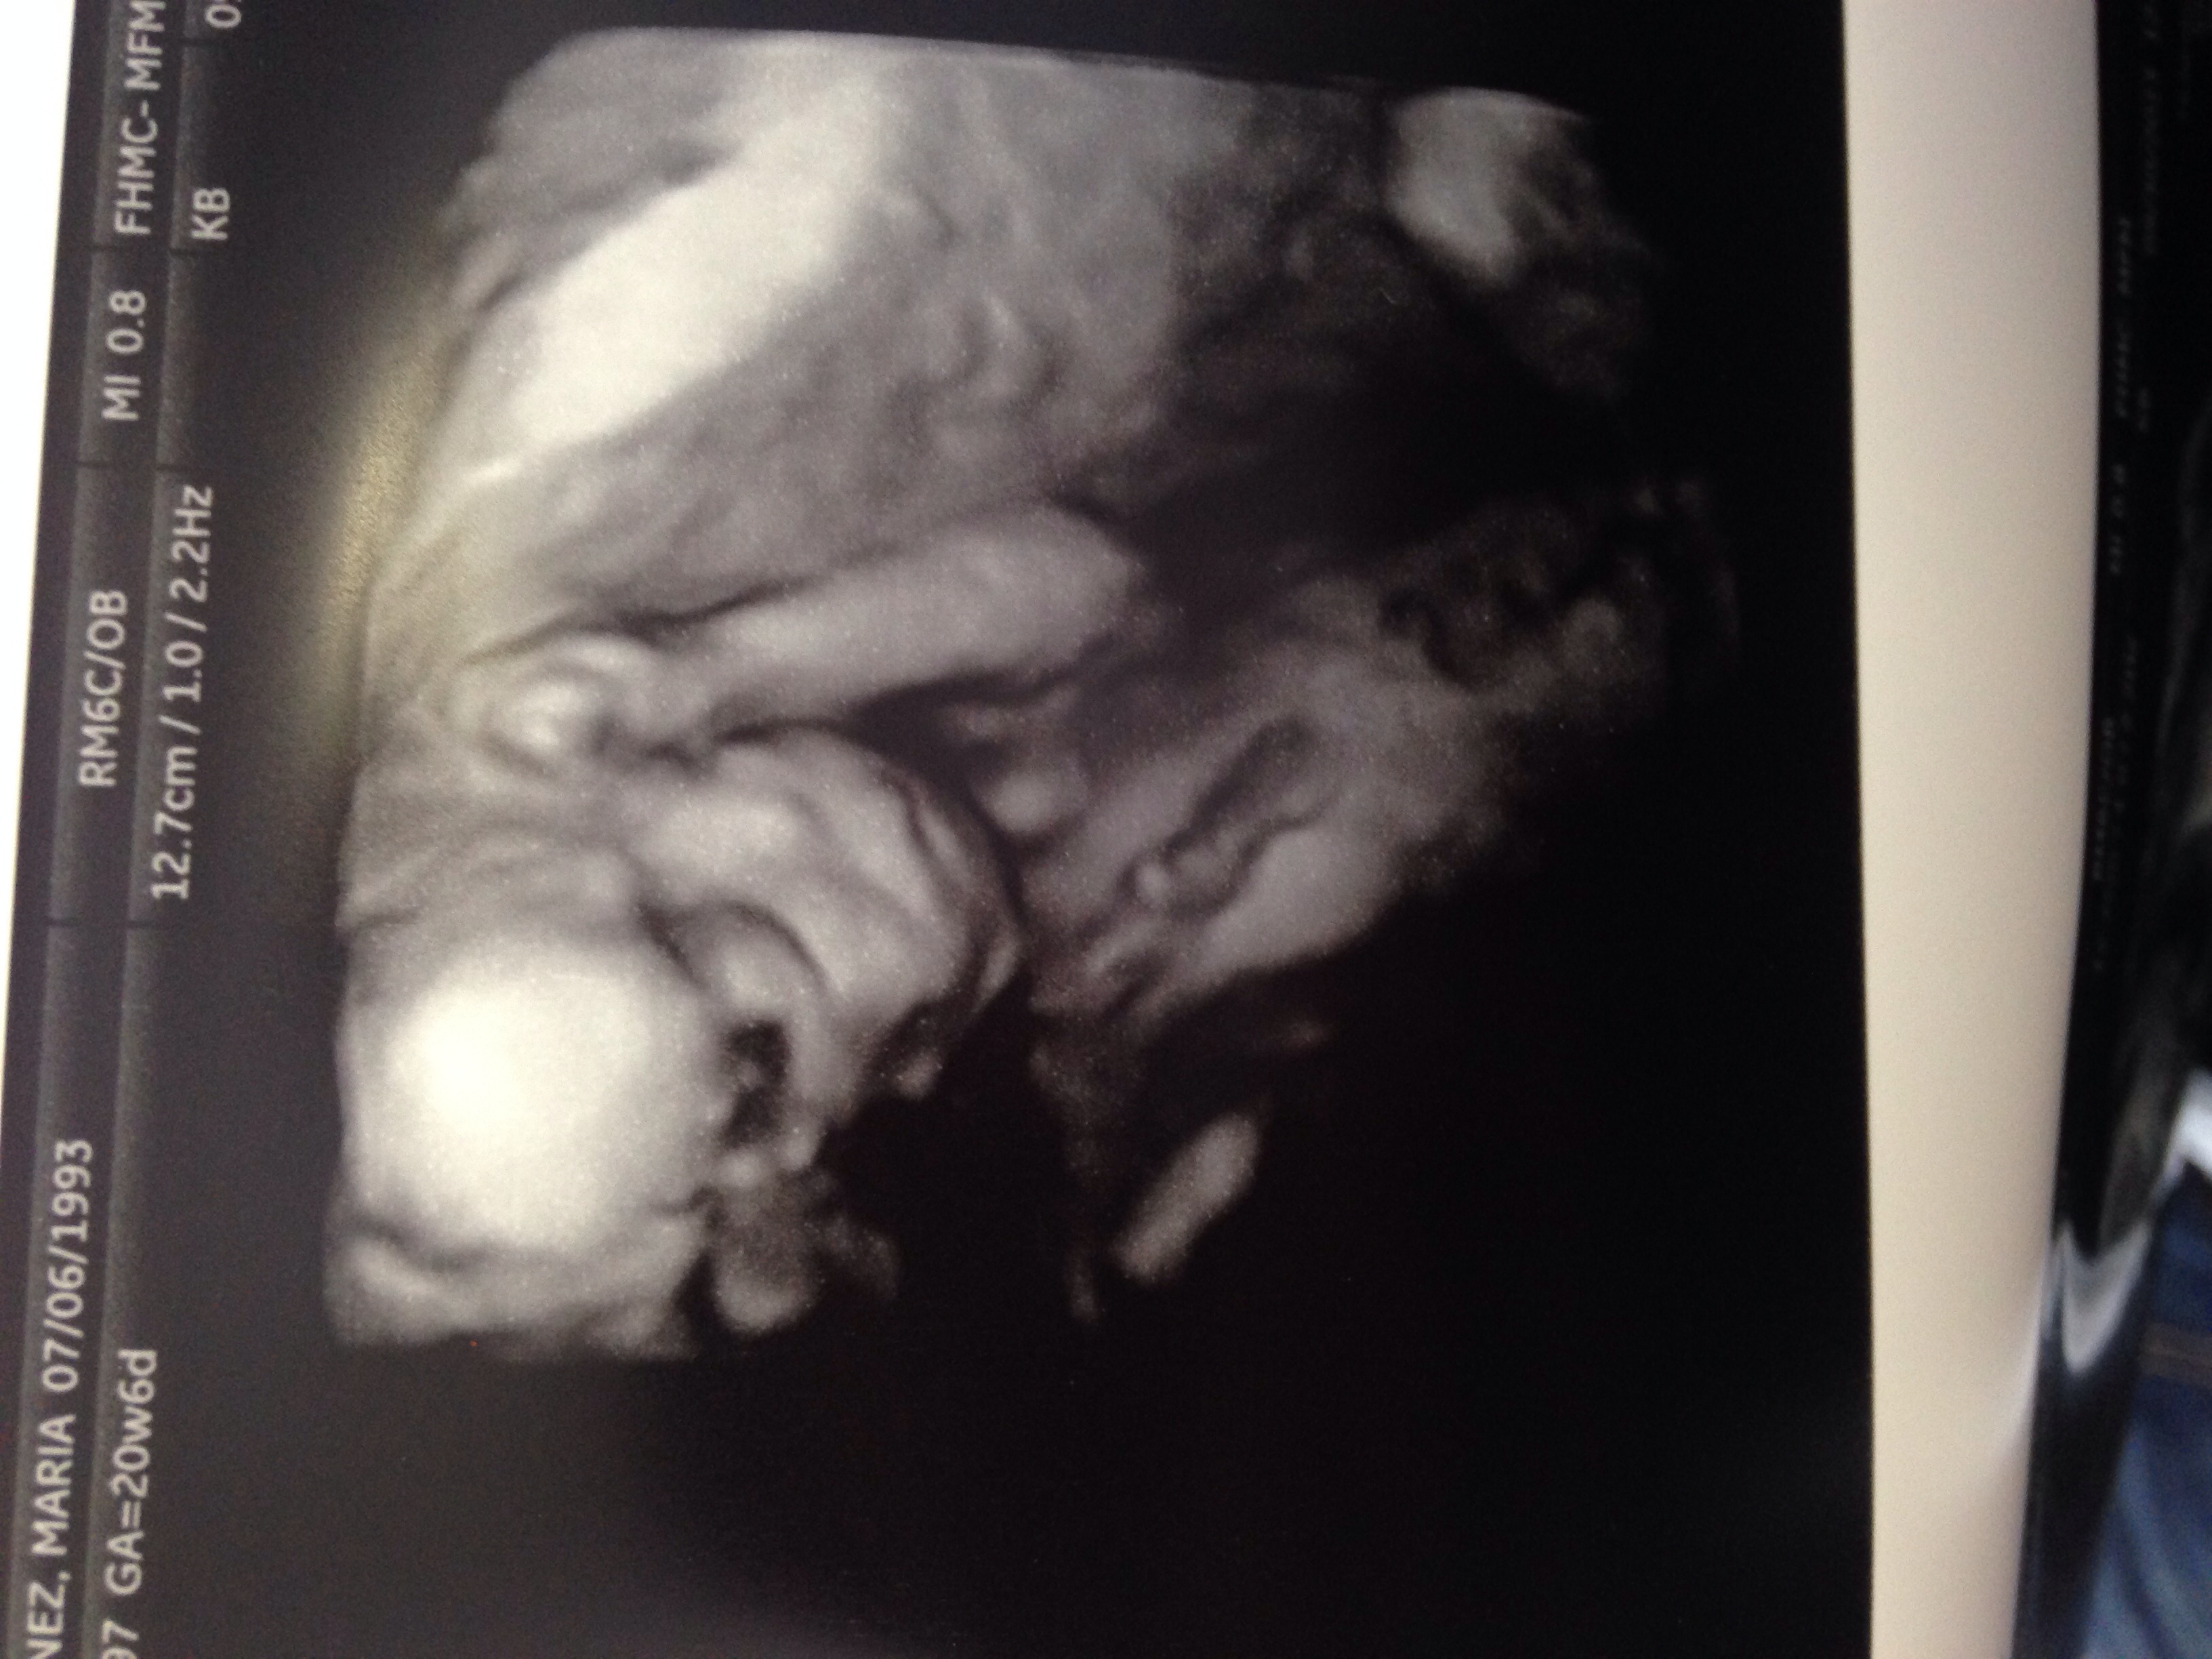

Here is out sweet little girl trying to hide from the camera